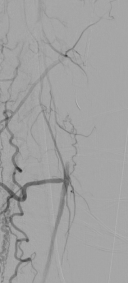

★ 病例 4

图:LA 基线造影

图:IVUS测量

图:Auryon Atherectomy System-减容

图:DCB扩张后的全程造影